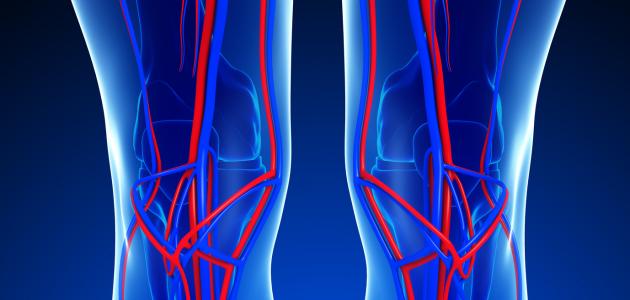

يحتاج الجسم لمادةٍ ناقلة تكون حلقة وصل بين المواد المُراد نقلها والأعضاء والخلايا المختلفة؛ حيث يؤدّي هذه الوظيفة المهمة الجهاز الدوراني في جسم الإنسان وهي شبكة واسعة من الأعضاء والأوعية الدموية، وهي مسؤولة عن تدفق الدم في جميع أجزاء الجِسم.

يُعتبر سريان الدم في أنسجة جسم الإنسان ذا أهميّةٍ كبيرةٍ لبَقاء جَميع الأعضاء حيّة، حيث أنها تنقل الأكسجين والهرمونات والغذاء والغازات الأخرى من وإلى الخلايا، ومن دون هذا الجهاز فإنّ الجسم يكون غير قادرٍ على مُحاربة الأمراض أو الحفاظ على استقرار الحرارة والحموضة والبيئة الداخلية للجسم.[٢]

تنقسم الدورة الدموية في الجسم إلى دورة دموية صغرى ودورة دموية كبرى وكان لاكتشاف آليّة عمل الدورة الدموية الثورة في مجال الطب؛ فكثيرٌ من الظواهر في جسم الإنسان تمّ تفسيرها بناءً على هذا الشرح.

تدور الدورة الدمويّة الصغرى بين الرئتين والقلب؛ حيث يَنقسم القلبُ إلى بُطين أيمن وبطين أيسر، وأذين أيمن وأذين أيسر، وتحمل الأوعية الدمويّة (الشريان الرئوي) الدم الذي يحتوي على ثاني أكسيد الكربون والسموم من البُطين الأيمن في القلب إلى الرّئتين لاستبدالها بدم يحتوي على الأكسجين والغذاء عن طريق تحرير ثاني أكسيد الكربون واتّحاد كُريات الدم الحمراء مع جزيئات الأكسجين من الرئتين، ثمّ تعود به الأوردة الرئوية إلى الأذين الأيسر في القلب مرّةً أخرى ليُوزّعه على باقي أجزاء الجسم من خلال الدورة الدموية الكبرى.[٥]

تدور الدورة الدموية الكبرى بين القلب وأجزاء الجسم المختلفة باستثناء الرئتين؛ حيث ينقل الشريان الأبهر الدم المليء بالأكسجين إلى الشرايين والشُعيرات الدموية التي تنتشر في جميع أجزاء الجسم لتوصيل الأكسجين إلى الخلايا من أجل إتمام عملية التنفس الخلوي داخل الميتوكندريا، وفي الوقت نفسه يتم امتصاص ثاني أكسيد الكربون عبر الأوردة الصغيرة التي تنقل هذا الدم المُلوّث بثاني أكسيد الكربون إلى الأوردة الدموية الأكبر ثم إلى الوريد الأجوف الأعلى والوريد الأجوف الأسفل ثمّ إلى قسم القلب الأيمن، الذي بدوره يبدأ الدورة الدموية الصغرى التي تستبدل الدم الذي يَحمل ثاني أكسيد الكربون بدمٍ يحمل الأكسجين.[٥]

يحتوي جهاز الدوران على أجزاء مهمة تُعتَبر من أهمّ الأجزاء الوظيفية في جسم الإنسان، وهي:[٥]

- الشرايين.

- الأوردة.

- الشعيرات الدموية.